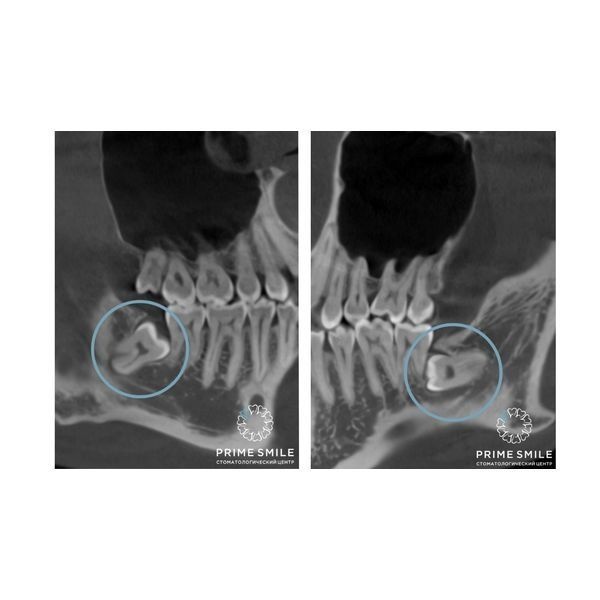

3D-диагностика нижней челюсти показала, что обе восьмёрки находились близко к нервам, корням и стенкам соседних зубов.

Ретенция и дистопия обоих зубов мудрости нижней челюсти.

Основная сложность состояла в том, чтобы при извлечении зубов не травмировать корни и стенки соседних зубов, а также не повредить нерв.

Ещё спустя неделю ему сделали 3D-диагностику челюсти, которая подтвердила успешность операции.